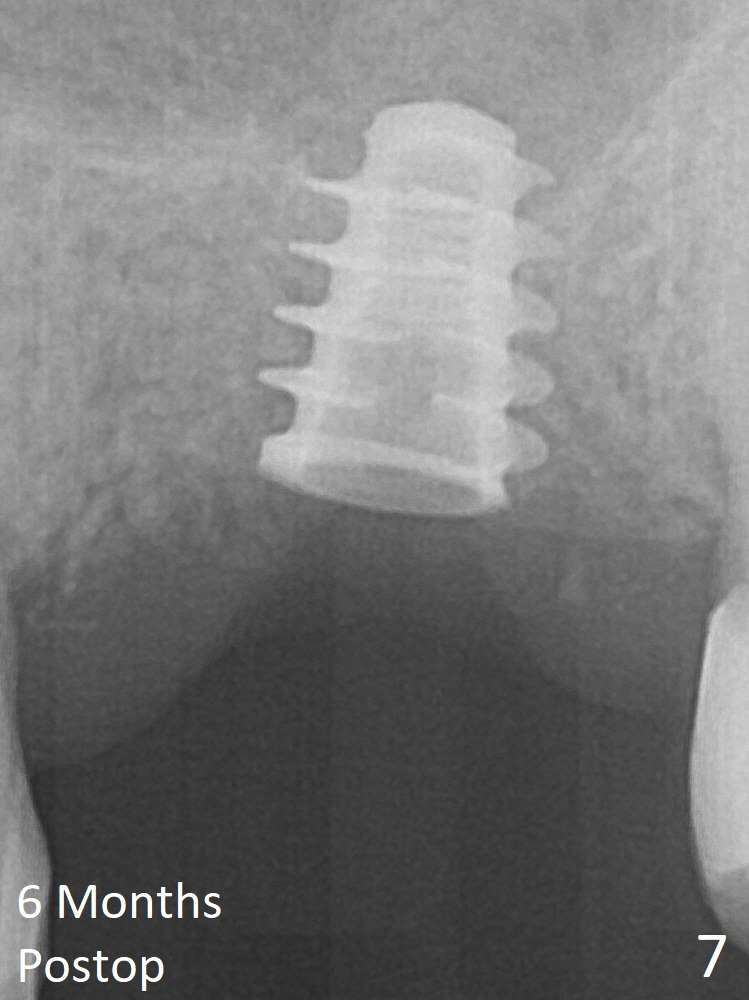

The implant is mobile 4 months postop (Fig.6).  A 6x2 mm healing abutment is placed.  Although the implant remains mobile 6 months postop, the bone seems to have become denser around the implant (Fig.7-9).  A healing screw is placed.